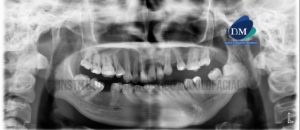

Paciente masculino de 17 años acude al Instituto de Diagnostico maxilofacial para evaluación imagenológica general. A la evaluación de la radiografía panorámica, evidenciamos que las